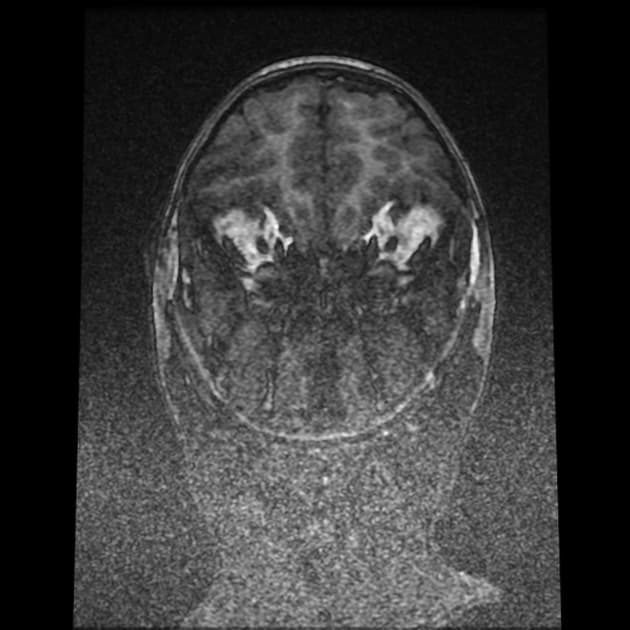

Temporal bone rhabdomyosarcoma with leptomeningeal metastases

Phía trước, khối u tiếp giáp với thùy thái dương dưới. Sự xâm lấn vào phía trong dẫn đến tiếp giáp với khoang động mạch cảnh bên trái, với các khoảng trống tín hiệu dòng chảy vẫn được bảo tồn trong các mạch máu lân cận. Xâm lấn ra phía trước ngoài liên quan đến tuyến mang tai kèm theo một hạch bạch huyết tuyến mang tai lớn. Có tăng quang màng não dạng nốt dày dọc theo lều tiểu não bên trái, thân não, màng não vùng nền, vòm sọ và bán cầu tiểu não, phù hợp với lan tỏa màng não mềm.

Các khối u cạnh màng não có nguy cơ xâm lấn nội sọ và lan tỏa màng não mềm cao hơn, như đã thấy trong trường hợp này. Hình thái dạng thùy, tăng quang không đồng nhất, bao quanh mạch máu nhưng vẫn bảo tồn khoảng trống tín hiệu dòng chảy, lan truyền quanh dây thần kinh và nền sọ, liên quan hạch vùng và tăng quang màng não dạng nốt lan tỏa là những đặc điểm của bệnh giai đoạn muộn. Sự xâm lấn nội sọ vào góc cầu tiểu não và các cấu trúc hố sau, cùng với hiệu ứng khối lên thân não và não thất tư, phản ánh tính chất xâm lấn mạnh. Di căn màng não mềm ảnh hưởng đáng kể đến việc phân giai đoạn và tiên lượng, đồng thời đòi hỏi chẩn đoán hình ảnh toàn bộ trục thần kinh và quản lý ung thư đa chuyên khoa.

Sarcoma cơ vân xương thái dương (temporal bone rhabdomyosarcoma) kèm di căn màng não (leptomeningeal metastases)